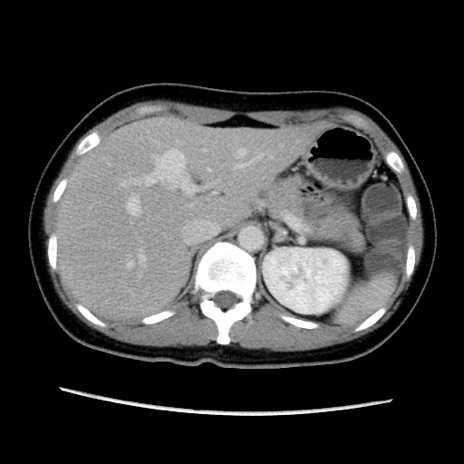

症例39(横断像)

【症例】40歳代女性

【主訴】上下腹部痛

【現病歴】2日目から下腹部痛あり。夜間は痛みで眠れなかった。昨日より上腹部痛と下痢が出現。臥位で痛みは軽快したため、休んでいた。本日になって臥位でも立位でも痛みが強くなってきたため救急要請。

【既往歴】子宮内膜症

【身体所見】部:平坦・軟、左上下腹部に圧痛あり、反跳痛あり。

【データ】WBC 21800、CRP 26.78